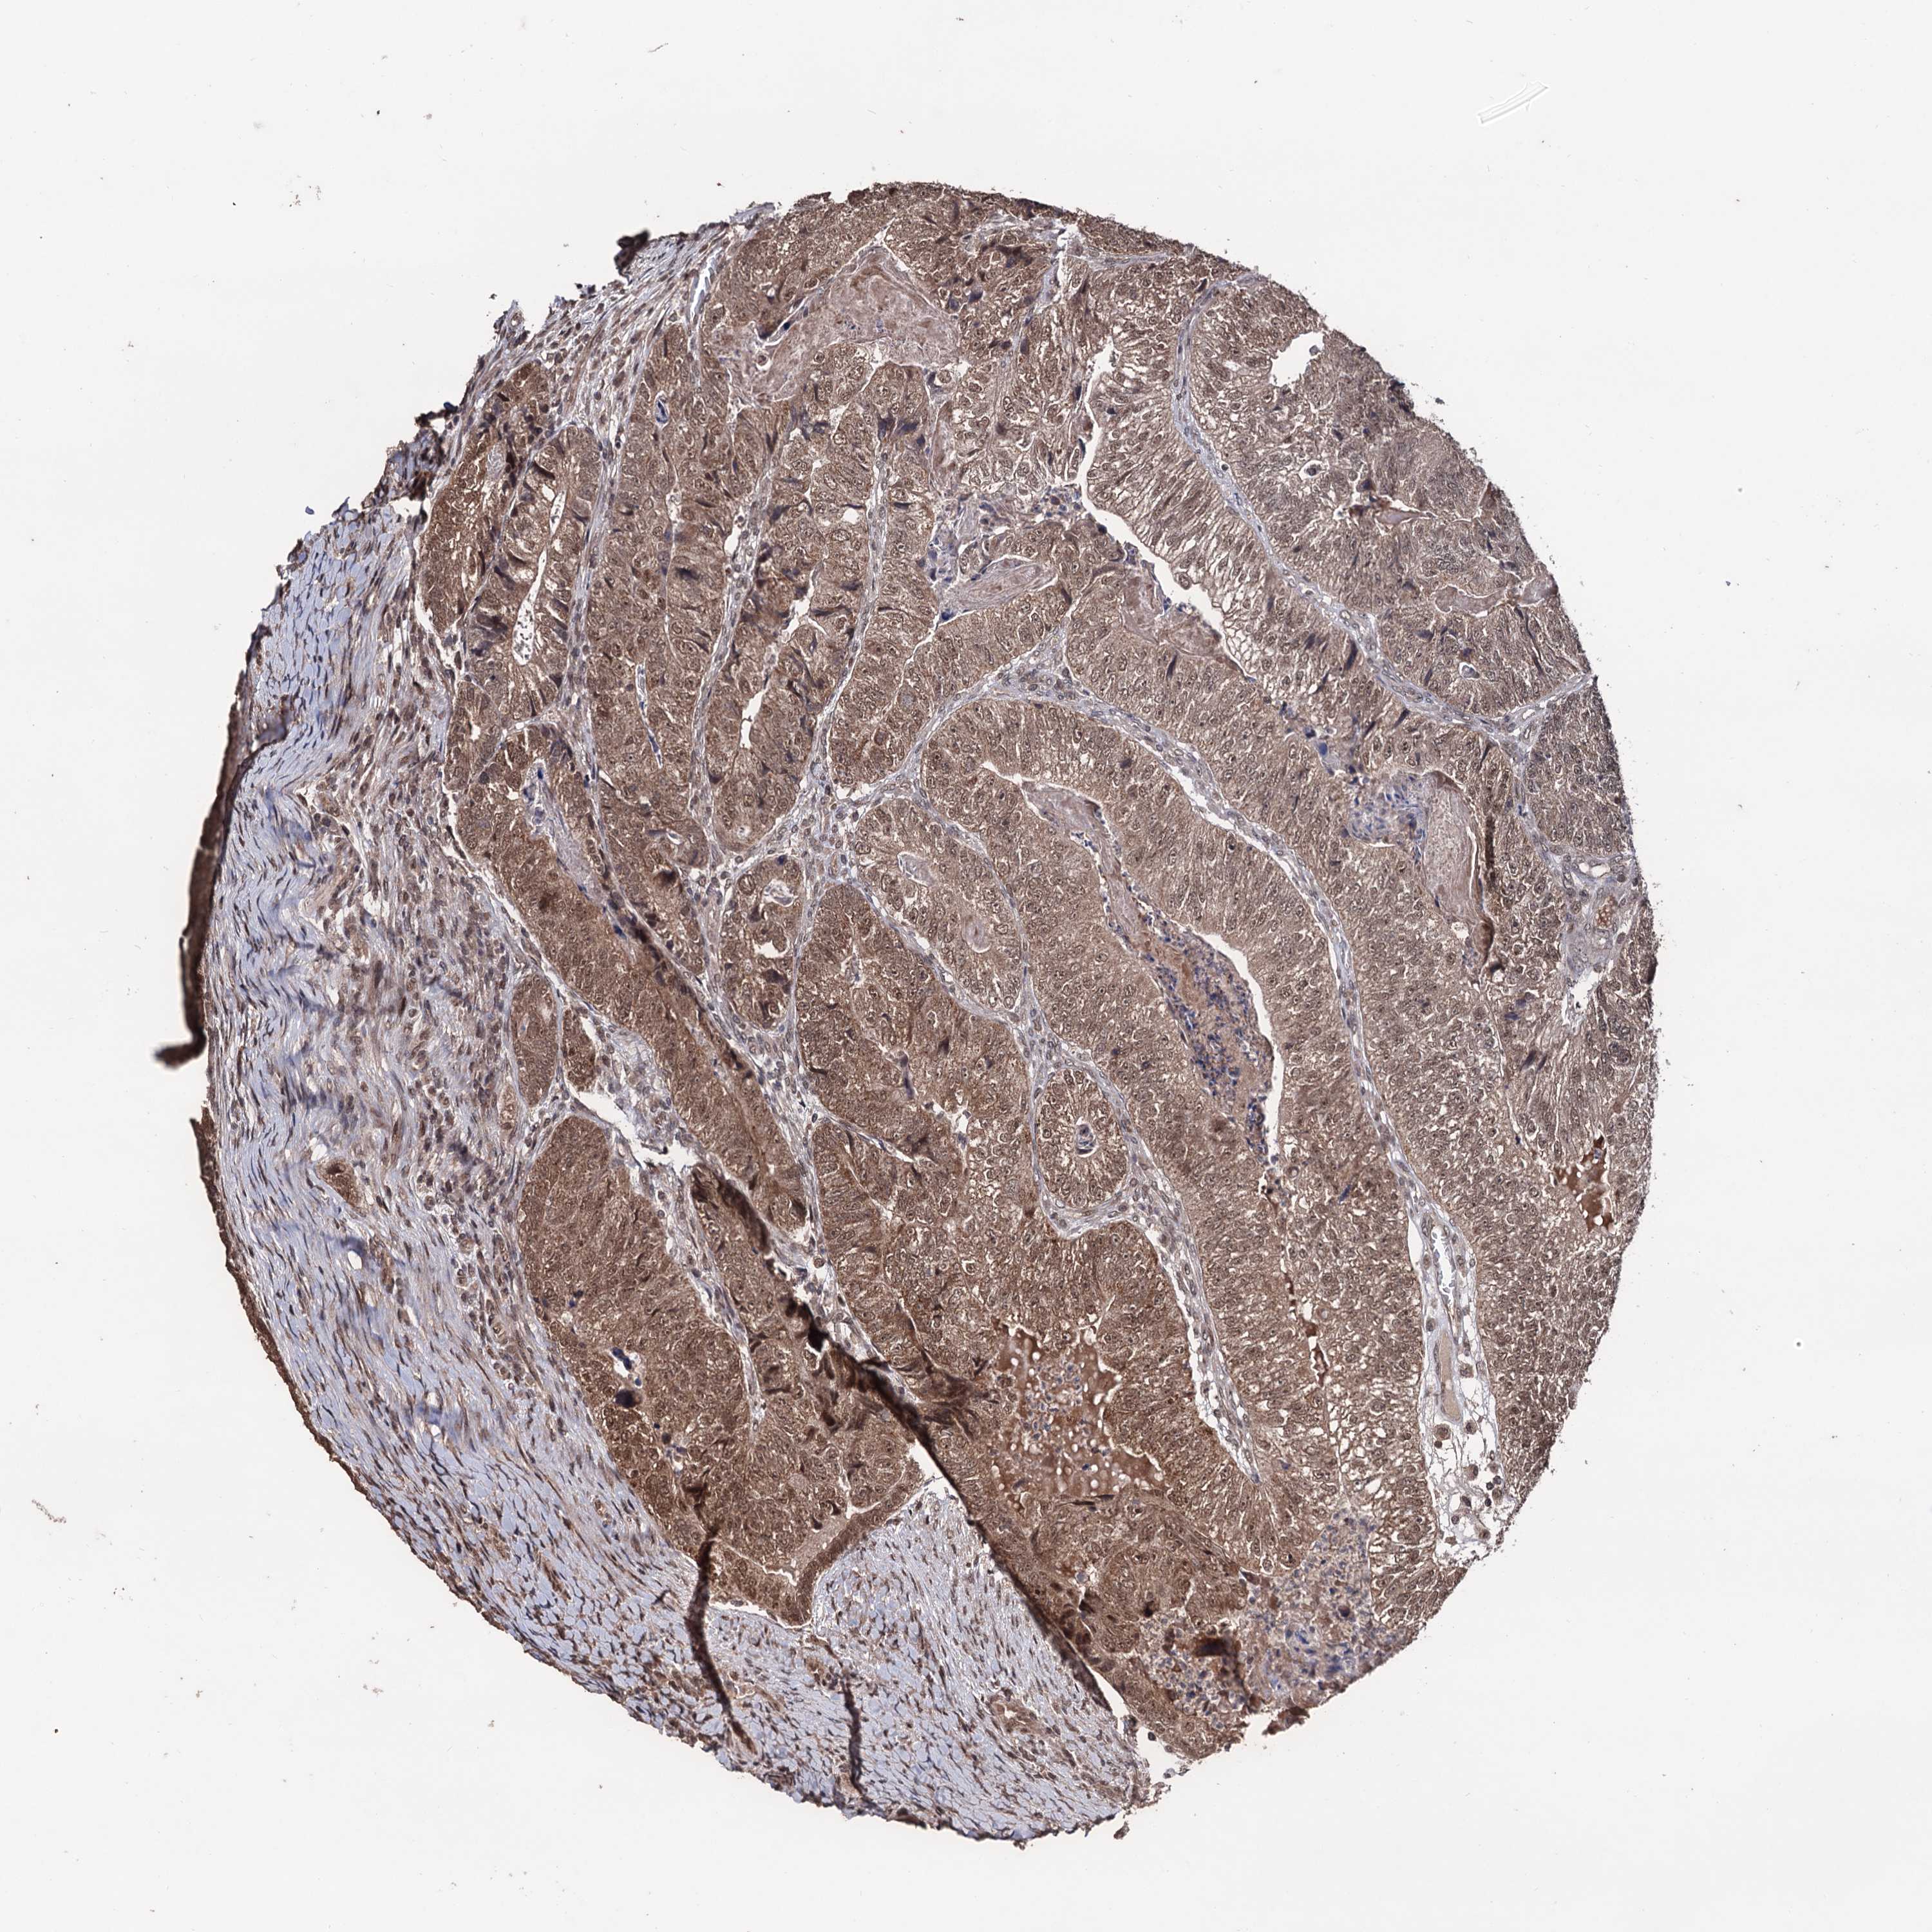

CANCER COLORECTAL CANCER Show tissue menu

Colorectal cancer

Human cancer

Colon adenocarcinoma

Rectum adenocarcinoma